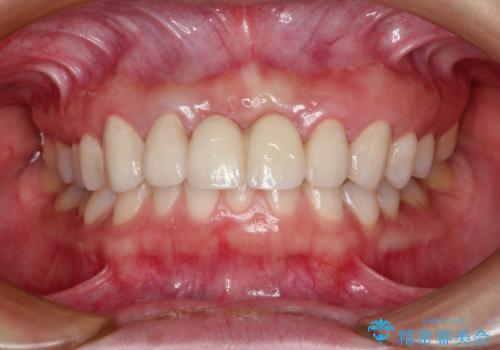

前歯 ブリッジ周囲の腫れた歯ぐきを改善

- 数ヶ月前に治療終了したブリッジの歯ぐきの違和感が強く、改善を求めて来院されました。

歯ぐきは著しく腫れ、少し触ると出血してしまうような状態であったためブリッジの再作製・歯周外科を用いた歯肉環境の改善を計画します。